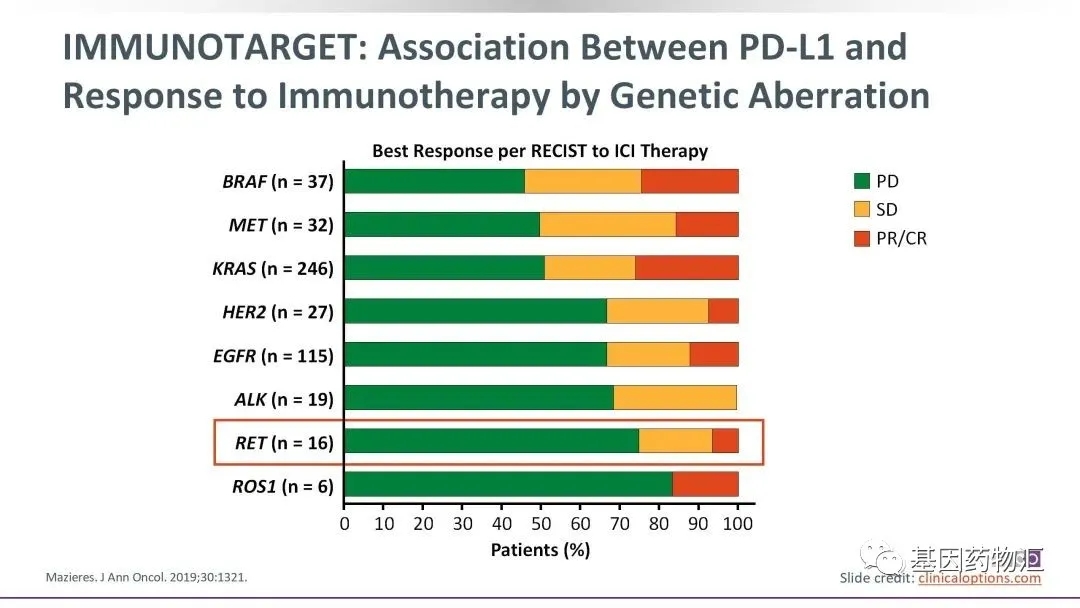

但相同的免疫治疗,对于不同突变类型的患者的效果也不一样。2019年公开结果的IMMUNOTARGET试验,就评估了各常见突变类型的非小细胞肺癌患者接受免疫治疗的响应率。

我们可以从结果中看出,BRAF和KRAS突变的患者对于免疫治疗的响应率比较高,整体的缓解率在20%~30%;MET、RET、HER2、EGFR、ALK、ROS1这些突变类型的患者,对免疫治疗的响应率比较低,在10%上下,但事实上这个问题并不严重,因为这些突变类型的患者,靶向治疗的选择非常丰富。

NTRK融合突变在肺癌当中本来就比较罕见,这类患者接受免疫治疗的临床试验更少。部分回顾性研究当中指出NTRK突变患者表现为微卫星稳定(MS-S)的概率比较高,这是一种免疫治疗效果不理想的标志。

但整体来说,如我们文首病例中所提出的那样,许多NTRK融合突变的患者,并不能如理想中一般,从指南推荐的免疫治疗方案当中获益。